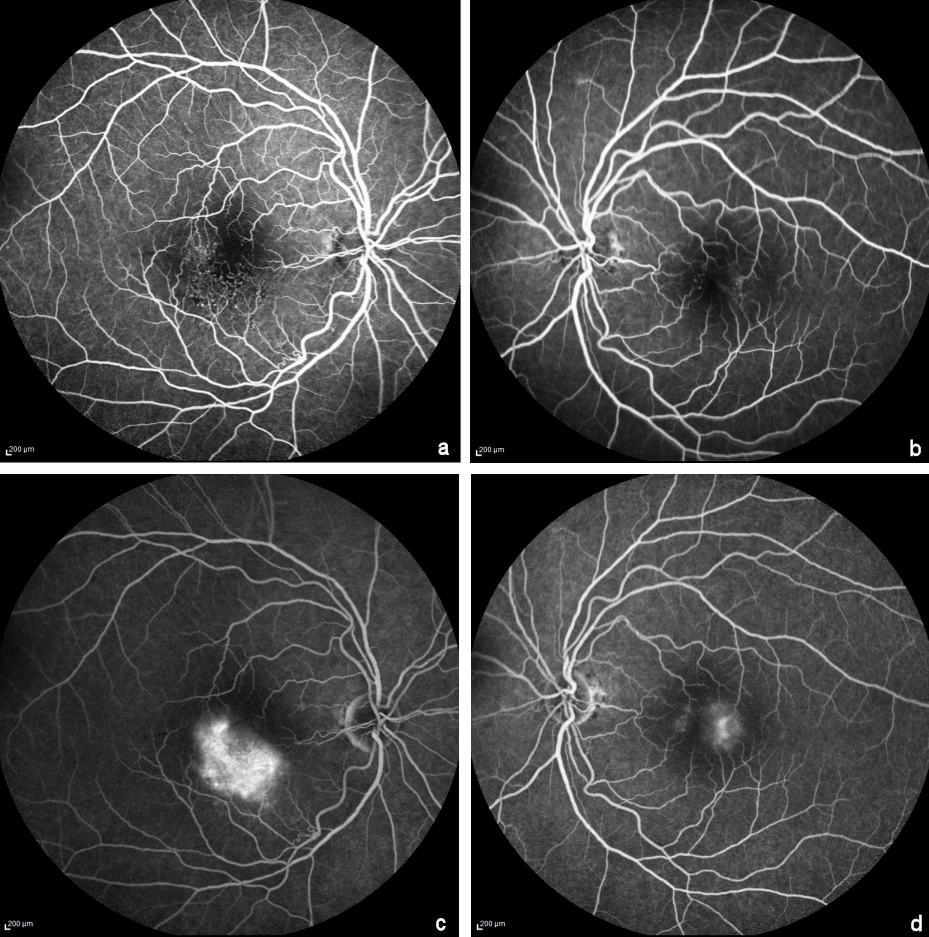

Figure 3: Fundus Fluorescein angiography early (a,b) and late phase (c,d).

In the right eye, telangiectatic vessels in the temporal and inferior parafovea with few microaneurysms are seen in the early phase (a). In the left eye, microaneurysms in the parafoveal region are seen in the early phase (b). Late phase images show diffuse hyperfluorescence in the right eye (c) and mild staining of the temporal parafovea in the left eye (d).

MC imaging (Heidelberg Engineering, Heidelberg, Germany) of the right eye showed a greenish hue inferior to the fovea corresponding to foveal thickening on spectral domain optical coherence tomography and yellow dots corresponding to the hard exudates (Figure 2a [Fig. 2]). In the left eye, MC imaging showed the microaneurysms (Figure 2b [Fig. 2]). In the blue reflectance images, an increased parafoveal reflectance was seen in both eyes (Figure 2c,d [Fig. 2]). Additionally, in the right eye it showed a clear distinction between hyperreflective vessels in the inferior parafovea and the hyporeflective appearance of normal vessels in the blue reflectance images. Early phase fundus fluorescein angiography in the right eye showed telangiectatic vessels in the temporal and inferior parafovea with few microaneurysms and diffuse late phase hyperfluorescence that corresponded partly to the area of foveal thickening on optical coherence tomography and partly to the hyperreflective area on blue reflectance (Figure 3a,c [Fig. 3]). In the left eye, early phase fundus fluorescein angiography showed micoaneurysms in the parafoveal region and mild staining of the temporal parafovea in the late phase (Figure 3b,d [Fig. 3]).